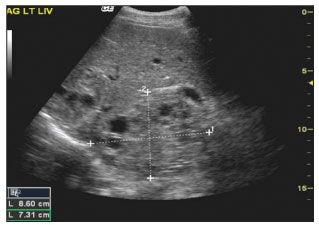

Figure 2 – An ultrasonogram of the liver shows a large echinococcal cyst in the left lobe.

He was afebrile, and findings from his physical examination were remarkable only for a well-healed posterior thoracic scar on the left side and tender hepatomegaly. Laboratory tests revealed a white blood cell count of 8500/µL, with a total eosinophil count of 510/µL; normal electrolyte, bilirubin, and aspartate aminotransferase levels; and a mildly elevated alanine aminotransferase level. Results of a serum antibody test for E granulosus were positive. The chest radiographic findings were normal. A CT scan (Figure 1) and an ultrasonogram (Figure 2) of the abdomen demonstrated multiple daughter cysts in both the left and right lobes of the liver. Magnetic resonance angiography (MRA) of the chest showed multiple intraluminal echinococcal cysts in the right pulmonary artery extending to apical branches of the right upper lobe pulmonary artery (Figure 3).